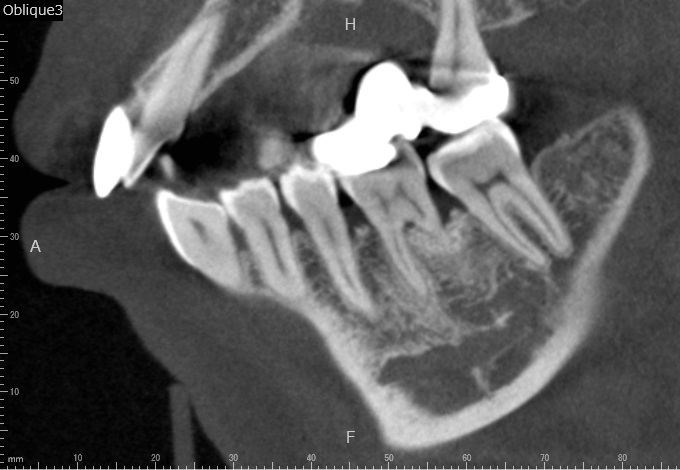

Case2

術前

術中

術後

| 治療名 | 再生療法 |

|---|---|

| 治療説明 | 右下6に重度の歯周病があり、通常の歯周治療でも改善しませんでした。歯周組織再生療法を行い、吸収してしまった骨を再生し、今後の歯周病の進行リスクを減らす事ができました。歯肉退縮もあったため同時に結合組織を移植し、骨と歯肉の再生を同時に行っています。 |

| 治療回数・期間 | 6ヶ月 |

| 副作用とリスク | 手術後に出血、腫脹、疼痛が生じることがあります。手術後は術部の創傷安定のためにブラッシング制限、食事制限があります。手術が複数回となることがあります。 |

| 料金(税込) | 再生療法:165,000円 結合組織移植:55,000円 総額:220,000円 |